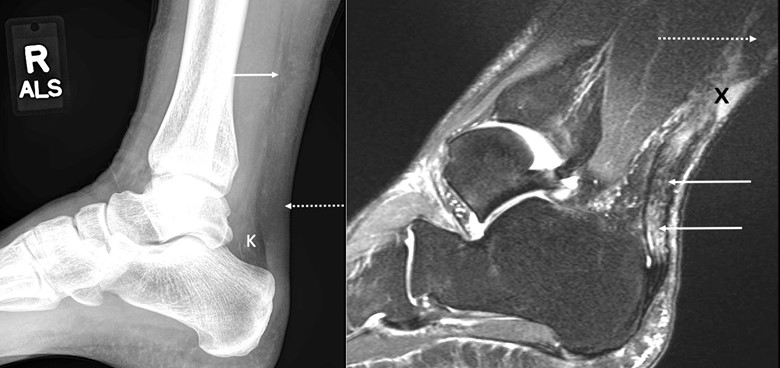

Because the Achilles tendon is bound by the Kager fat pad anteriorly and subcutaneous fat posteriorly, an abnormal appearance can often be detected on radiographs [12]. The lateral radiograph—left image above—demonstrates diffuse fusiform thickening of the Achilles tendon (dashed arrow). More proximally, the tendon is irregular anteriorly, consistent with a tear. There is edema in the Kager fat pad (“K”), also indicating acute tear. It can be difficult to determine partial versus full-thickness tear, and in this case, the posterior margin of the tendon appears intact, suggesting that it is a high-grade partial, rather than full-thickness tear, although MRI later confirmed that it was a full-thickness tear. Ossific foci, if present, suggest chronic tears (not seen in this case) [13].

The sagittal T2 fat-suppressed image—right image above—demonstrates a full-thickness tear (“X”) and severely degenerated proximal (dashed arrow) and distal (solid arrows) tendon. The uniformly thickened and hyperintense distal tendon is probably a combination of chronic tendon degeneration and acute edema from the tear, especially as individual fibers within the tendon are relatively well seen. It is important to comment on tendon quality and the length of tendon, which appears severely degenerated, because this tendon may not be useable for repair [14]. Many of the internal strands appear wavy, compatible with retraction. MRI is considered the gold standard for imaging Achilles tendon tears (sensitivity, 80–100%; specificity, 100%) (8, 15). Ultrasound also has high sensitivity (full thickness, 95%; partial thickness, 94%) and specificity (full thickness, 99%; partial thickness, 97%) for the detection of Achilles tendon tears, given the tendon’s superficial location and possibility of dynamic imaging with the modality (16, 17). This patient’s tear was also well seen on ultrasound (not shown).